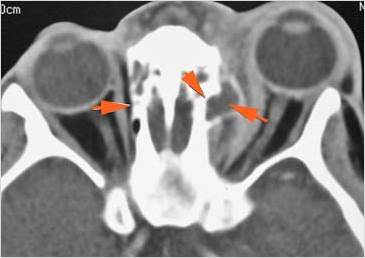

The superior and/or inferior ophthalmic veins are dilated or thrombosed.

Eyes

Proptosis is present.

The optic nerve is stretched in appearance.

Signs of tension orbit or endophthalmitis are present.